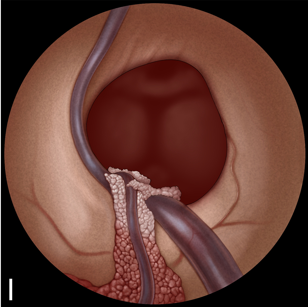

施罗德教授多幅精美插图展示了胶样囊肿切除的手术步骤:

A:检查室间孔,可见胼胝体(F)、脉络丛(CP)、透明隔静脉(SV)和丘纹静脉(T)。室间孔被胶样囊肿(C)阻塞。

B:用双极电凝脉络丛。

C:用剪刀切开囊肿包膜。

D:用吸引管吸出囊肿内容物,像一颗剥壳荔枝。(右侧为真实术中场景)。

E:将囊肿移入侧脑室。

F:采用双手手术技术暴露囊肿蒂。通过左侧通道插入一把可弯曲的抓钳。主要手术器械通过 2.9 毫米的直工作通道引入。

G:用双极电凝器采用双手手术技术凝固囊肿蒂。

H:用剪刀采用双手手术技术切断囊肿蒂。

I:囊肿切除后检查室间孔。